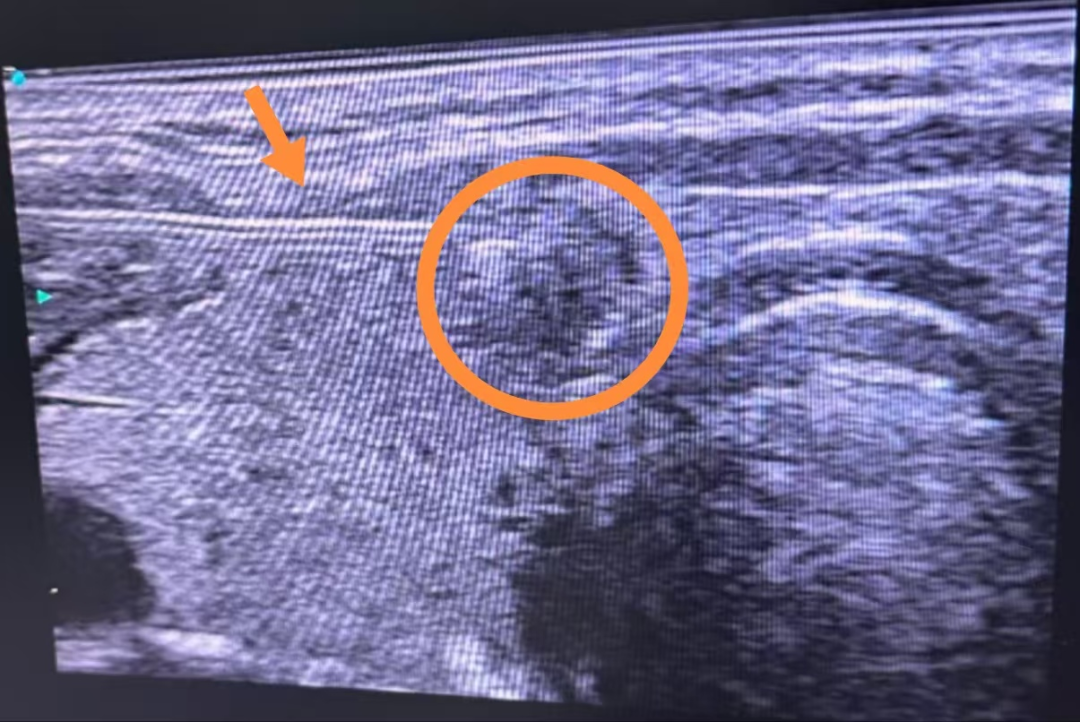

近日,我院普外科再次成功为一例甲状腺肿物患者实施了超声引导下甲状腺穿刺活检术(FNA)。此次手术在超声的实时精准引导下顺利完成,术后病理科迅速反馈结果为甲状腺乳头状癌,为患者的后续治疗提供了关键依据。

甲状腺穿刺活检术(FNA)是一种在超声引导下,通过细针穿刺获取甲状腺组织样本进行病理检查的技术。它是诊断甲状腺结节良恶性的“金标准”,能够为临床治疗提供重要依据。

1.精准定位,确保无误。借助先进的高分辨率超声设备,医生能够清晰观察到甲状腺结节的精确位置,从而确保穿刺过程的准确无误。

1.高分辨率成像:能够清晰显示病灶及其周围组织,为医生提供准确的视觉引导。

2.实时引导功能:确保手术操作的精准性和安全性,提高了手术的成功率。